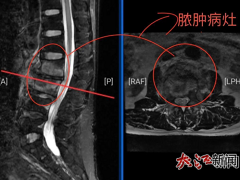

• 78岁老人患肺鳞癌,中西医结合显疗效